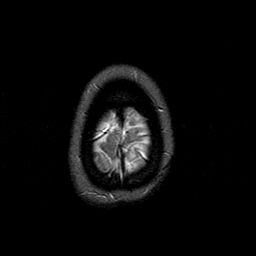

MR Study #1 -- Slice #48

[Home][Help][Clinical][Tour 1][Tour 2][Tour 3] Slice 48